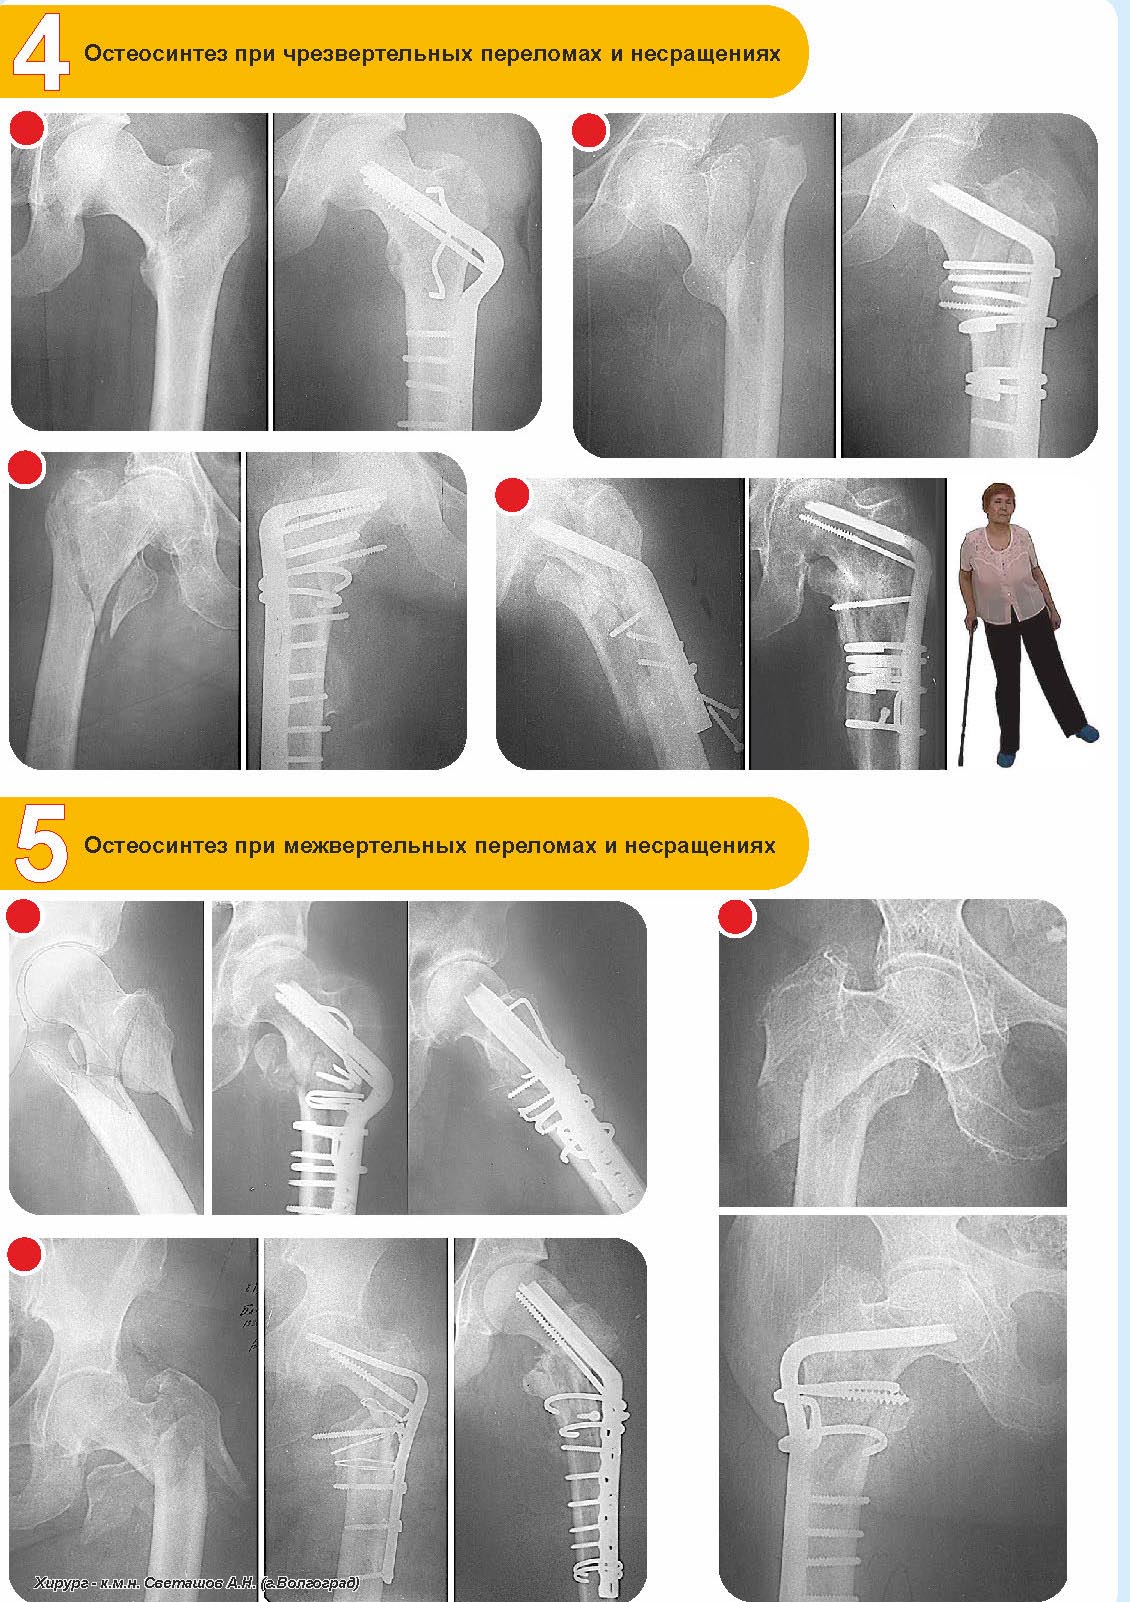

Imtamed 26 Ноябрь 2014, 10:43

Способы лечения